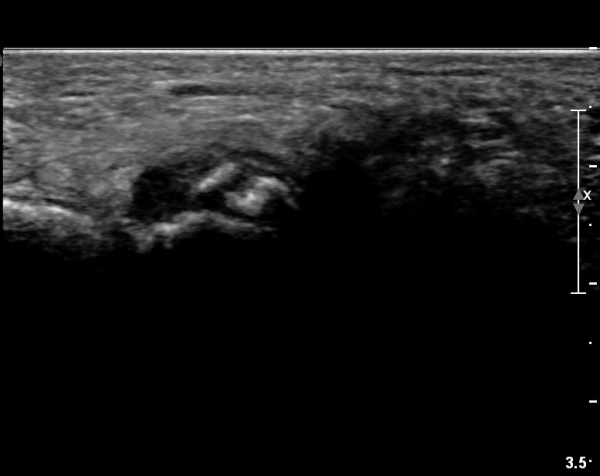

ÃÊÀ½ÆÄ °Ë»ç

±¹¼ÒÀû ¾ÐÅëÀ» º¸ÀÌ´Â ÁßÁ·°ñÀÔ¹æ°ñ °üÀý ¹Ù´ÚÃø¿¡ ŽÃËÀÚ¸¦ ´ë´Ï Á¾ÀÚ»ÀÀÇ °¡ µÎ Á¶°¢À¸·Î

°üÂûµÇ°í Á¾ÀÚ»À ±ÙÀ§ºÎ¿¡ Àú¿¡ÄÚ ¿¬ºÎÁ¶Á÷ ºÎÁ¾ÀÌ °üÂûµÇ°í µÎ Á¾ÀÚ»À »çÀÌÀÇ »À Ç¥¸éÀÌ °ÅÄ£

¾ç»óÀ» º¸ÀÓ(»çÁø 1).

ÃÊÀ½ÆÄ°Ë»ç»ó Á¾ÀÚ»À³ª ºñ°ñ°Ç ÁÖÀ§ÀÇ ºÎÁ¾, Á¾ÀÚ»ÀÀÇ Ç¥¸éÀÇ °ÅÄ£Çü»ó, ºñ°ñ°ÇÀÇ ºÎÁ¾À̳ª ÆÄ¿­ÀÌ °üÂûµÉ ¼ö ÀÖ´Ù.